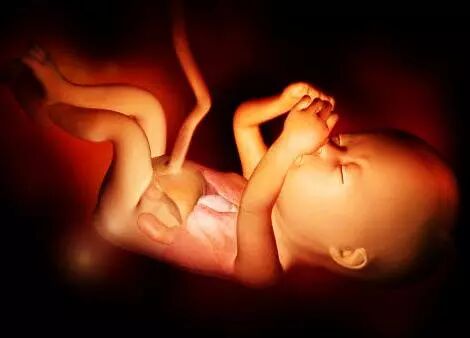

父母都希望自己的宝宝健健康康,所以,孕期定时产检,是最重要的事情了。整个孕期,宝妈们至少要进行3次或者3次以上的超声检查,其中孕中期的「四维彩超」最特别,这个检查是宝宝跟宝妈第一次「亲密接触」。透过先进的仪器,宝妈能直观的看到胎宝宝的模样和一举一动。

记录宝宝在妈妈肚子里的成长过程:四维彩超不仅可以让准妈妈感觉到宝宝的运动,而且可以亲眼目睹他们的一举一动和乖巧面容。另外还可以将宝宝的样子和动作制作成照片或录像,让宝宝拥有最完整的0岁相册,是很值得珍藏的。

一般来说,怀孕24-28周是照四维彩超的最佳时间,因为胎儿24周左右正是大脑突飞猛进的发育时期,这个时期的胎儿结构已经形成,胎儿的大小以及羊水适中,在宫内的活动空间较大,胎儿骨骼回声影响比较小,图像也比较清晰。